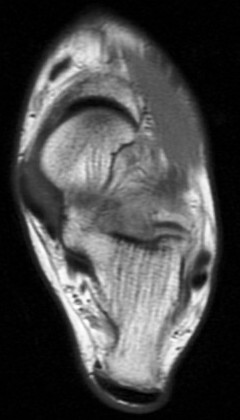

36 yo M s/p ankle sprain 7 months ago

Marked edema and scarring in the tarsal sinus. Has healed sprains of the ankle ligaments with scar remodeling (not shown). You can see where the ongoing pain is by the oil marker. I insist on having pain markers when possible. Reference article.

sinus tarsi syndrome ( RID3222 )